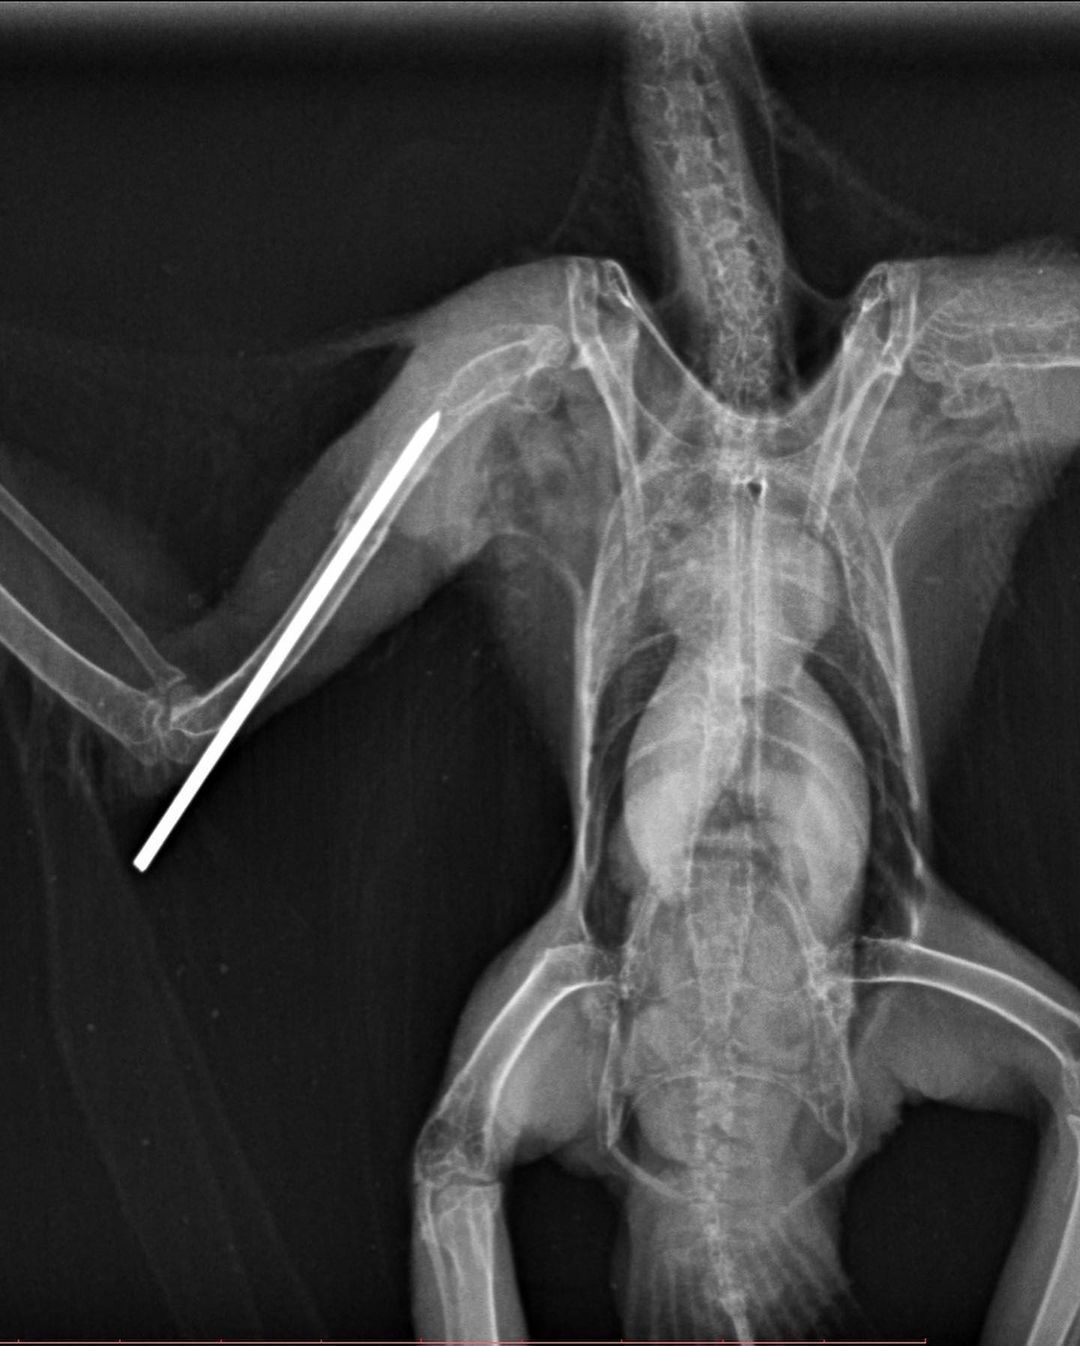

Une radiographie a été réalisée permettant de visualiser l’ensemble des os de l’aile et ainsi confirmer le diagnostic d’une fracture diaphysaire humérale. Concernant ses orteils, ils étaient sains et cicatrisés donc ne nécessitaient pas de soin particulier.

Une chirurgie réparatrice de l’humérus a été réalisée le jour suivant par l’une de nos vétérinaires faune sauvage, assistée par des étudiants. La pose d’une broche centro-médullaire va permettre de réaligner les fragments de l’os fracturé pour obtenir une consolidation osseuse. Afin d’immobiliser l’aile et favoriser une cicatrisation rapide, un bandage en 8 est renouvelé tous les deux jours. C’est à ce moment-là que l’équipe vétérinaire réalise également de la physiothérapie pour maintenir une bonne mobilité de l’aile.